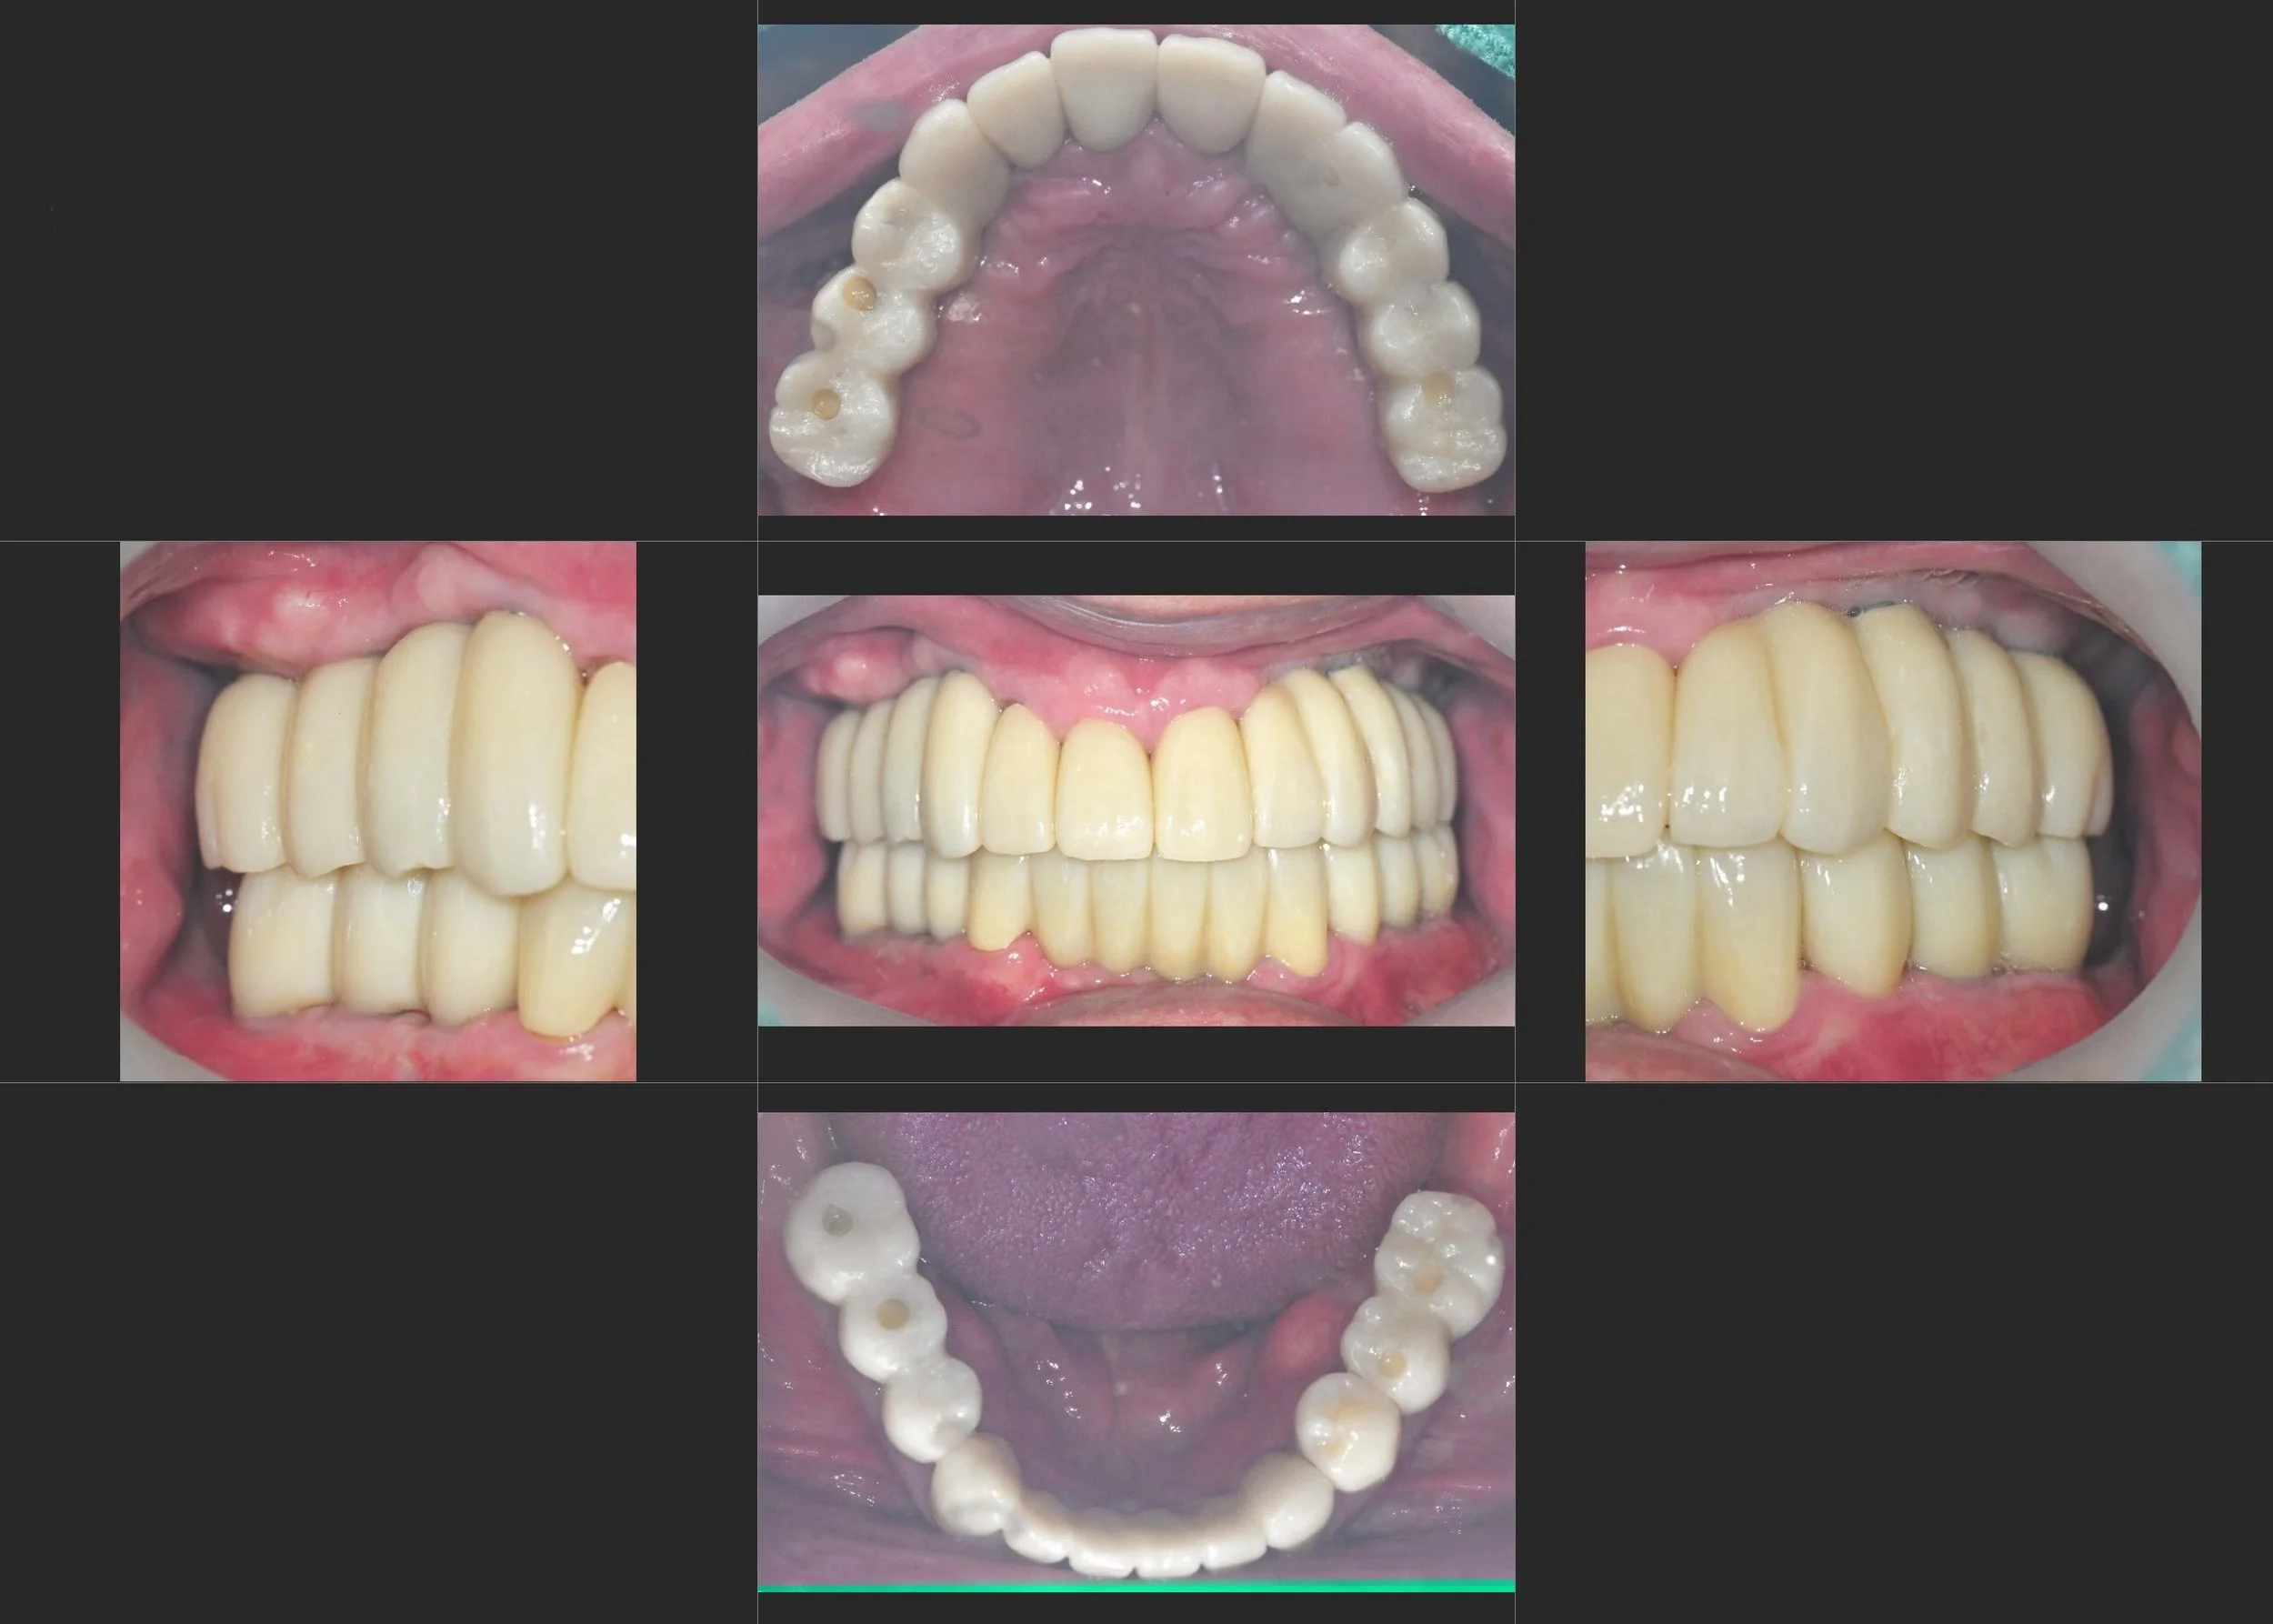

INTRA ORAL - BEFORE

The patient had lived for decades believing he had a skeletal Class III malocclusion.

Following multiple unsuccessful dental treatments, he relied on an ill-fitting removable prosthesis,

which ultimately led to severe deterioration of the remaining abutment teeth.

Clinical and radiographic assessment revealed a pseudo Class III occlusion,

rather than a true skeletal discrepancy.